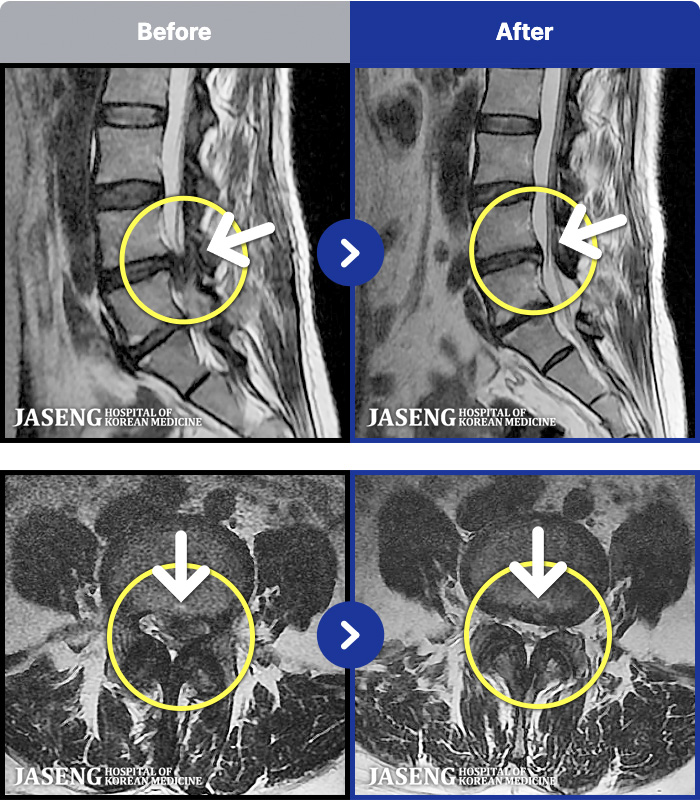

MRI ġ

1,237 MRI ũ ʸ Ȯϼ.